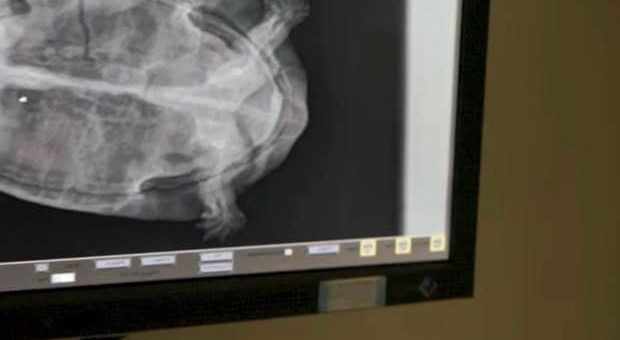

في واقعة غريبة من نوعها، تفاجأ الفريق الطبي العامل في أحد المراكز الطبية في جزيرة تينيريفي التابعة لجزر الكناري الإسبانية بوجود سلحفاة داخل رحم امرأة بريطانية الجنسية.

وكشفت صحيفة "ديلي ميل" البريطانية أنّ الشرطة الإسبانية في جزر الكناري فتحت تحقيقًا حول اعتداء جنسي وذلك بعد العثور على سلحفاة في رحم المرأة التي تبلغ من العمر 26 عامًا.

وفي التفاصيل، بدأت السيدة تشعر بشيء غريب داخل بطنها، بعد يومين من حضورها احتفالات مع أصدقاء بريطانيين في الجزيرة، وعليه، توجهت المرأة على الفور لأحد المراكز الصحية بجزيرة تنريفي، للخضوع إلى فحوصات بسبب شعورها بألم في أسفل بطنها.

وبعد إجراء الفحوصات اللازمة لها، فوجئ الفريق الطبي بوجود سلحفاة نافقة داخل رحمها، ما أدى إلى إصابتها بالتهابات جرّاء ذلك.